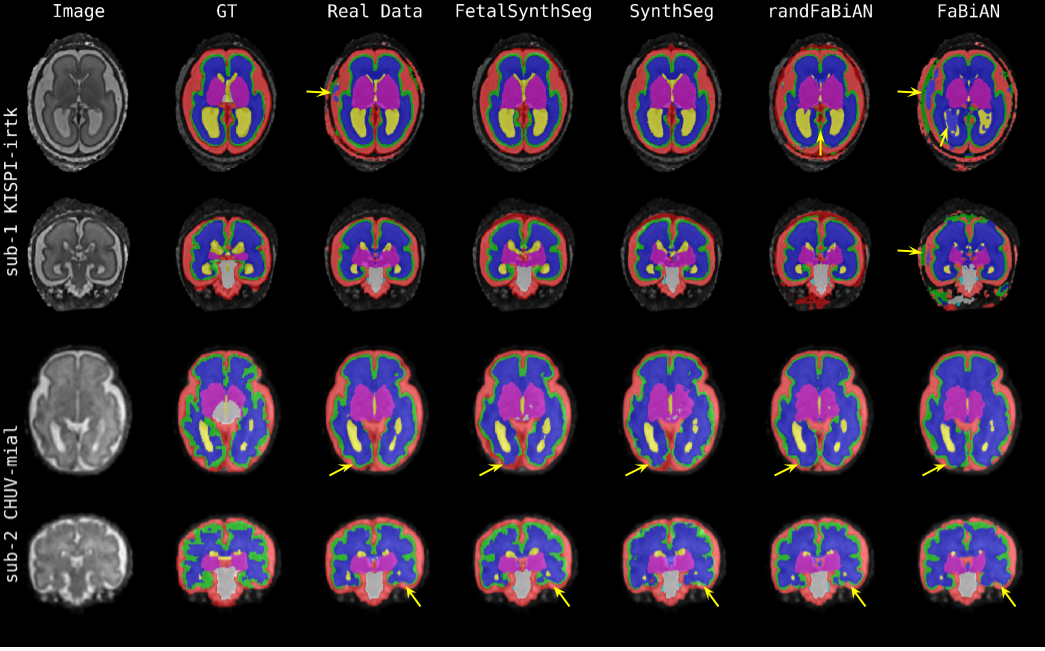

Qualitative analysis in Figure 6 illustrate these findings, showing that models with randomized contrast generators like randFaBiAN and FetalSynthSeg are more robust to domain shifts, particularly when there is a mismatch in skull-stripping quality between training and testing data.

Refer to caption

Figure 6: Segmentation results for models trained on the KISPI-MIAL data split, evaluated on a subject from the KISPI-IRTK split (top; excellent quality) and on another from the CHUV-mial split (bottom; acceptable quality). Arrows point to regions of substantial discrepancies across models.